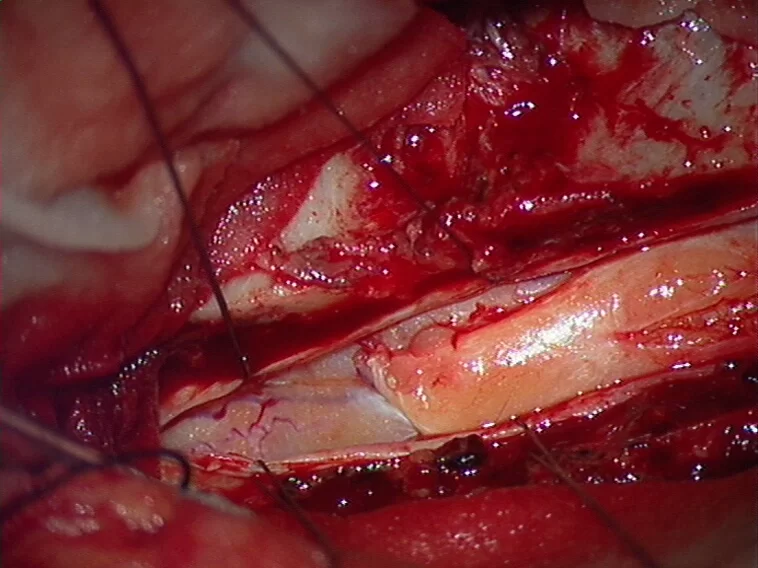

Οι ενδοσκληρίδιοι-εξωμυελικοί εντοπίζονται εντός της σκληράς μήνιγγας (δηλαδή του περιβλήματος του νωτιαίου μυελού) αλλά εκτός του νωτιαίου μυελού (Εικόνα 2). Η συχνότητα είναι περίπου 40% των όγκων σπονδυλικής στήλης. Οι πιο συχνοί τύποι είναι τα μηνιγγιώματα, τα επενδυμώματα του τελικού νηματίου, τα σβαννώματα και τα νευρινώματα. Πρόκειται στην πλειοψηφία τους για καλοήθεις όγκους.

Χειρουργική Αντιμετώπιση: Οι ενδείξεις και ο τρόπος χειρουργικής αντιμετώπισης εξαρτώνται απολύτως από τον τύπο του όγκου. Πρωτοπαθείς (μη-μεταστατικοί) όγκοι των σπονδύλων χρειάζονται ριζική αφαίρεση με σπονδυλεκτομές. Σε περίπτωση μεταστάσεων συνήθως αρκεί η αποσυμπίεση των νευρικών δομών και η συμπληρωματική ακτινοβολία. Το αν υπάρχει ένδειξη για χειρουργείο σε ασθενή με μεταστατική νόσο σπονδυλικής στήλης είναι κάτι που πρέπει να συζητηθεί και να συναποφασιστεί με τους ογκολόγους. Για ενδοσκληρίδους όγκους όπως πχ. μηνιγγιώματα ή νευρινώματα, καθώς επίσης για ενδομυελικούς όγκους (πχ. αστροκυττώματα ή επενδυμώματα) η θεραπεία είναι η ολική χειρουργική αφαίρεση. Συνήθως χρησιμοποιούνται ελάχιστα επεμβατικές μέθοδοι ενώ αποφεύγεται η καταστροφή των υγιών ιστών και δομών της σπονδυλικής στήλης (Εικόνα 3). Μερικοί όγκοι, όπως πχ. το λίπωμα νωτιαίου μυελού, αφαιρούνται ιδιαίτερα αποτελεσματικά με τη χρήση λέιζερ (laser) (Εικόνα 4).